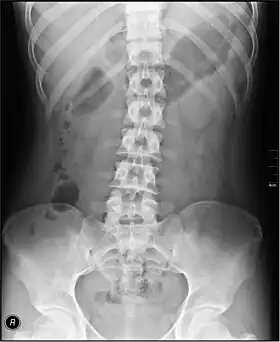

• Lumbar Spine - AP and Lateral +/- L5/S1 view in the UK, with obliques and Flexion and Extension requests being rare.[15] In the US, basic projections include an AP, two Obliques, a Lateral, and a Lateral L5-S1 spot to better visualize the L5-S1 interspace. Special projections are AP Right and Left bending, and Laterals with Flexion and Extension.

• Pelvis - AP only in the UK, with SIJ projections (prone) on special request.[15]